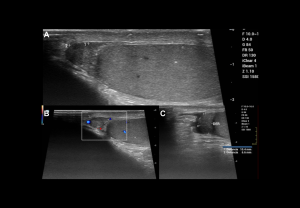

DOPPLER EVALUATION

Assessment of testicular perfusion is a critical component in acute scrotal pain.

Flow characteristics:

- Intratesticular arteries: Low-resistance waveform with continuous diastolic flow; peak velocities 3–5 cm/s; RI 0.4–0.7.

Doppler findings:

- Degree of torsion:

- Complete (≥360°): Usually absent intratesticular flow.

- Partial (<360°): Residual intratesticular flow may be detectable.

- Spectral Doppler: Increased resistive index (RI) and possible diastolic flow reversal, whirlpool sign of spermatic cord

- Doppler: Diffuse hyperaemia, low-resistance arterial flow (RI: epididymis <0.7, testis <0.5).